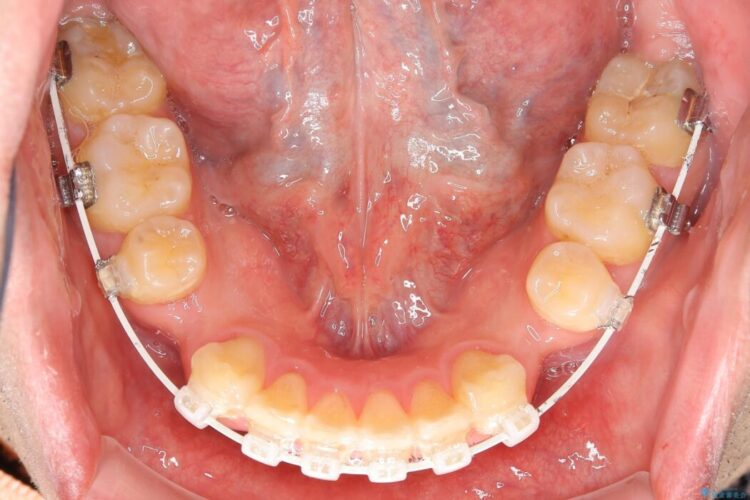

【30代男性】ワイヤー矯正で出っ歯とガタつきの改善

上の歯の出っ歯と下の歯のガタつきが気になるとご来院された患者様です。

出っ歯とガタつきの改善には抜歯が必要と診断し、上下左右第一小臼歯を抜歯することとしました。

抜歯でスペースができるため、歯の移動量が多いことから表側ワイヤー矯正装置で治療を行いました。